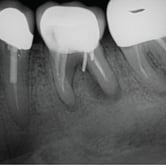

Calcificación Pulpar

La calcificación pulpar es la formación de depósitos de calcio dentro de la pulpa dental, que puede dificultar el tratamiento de conducto.

Los pacientes generalmente no tienen síntomas, pero pueden experimentar sensibilidad.

El tratamiento incluye la eliminación de los depósitos durante el tratamiento de conducto. Es importante tratarlo para evitar complicaciones durante el procedimiento.